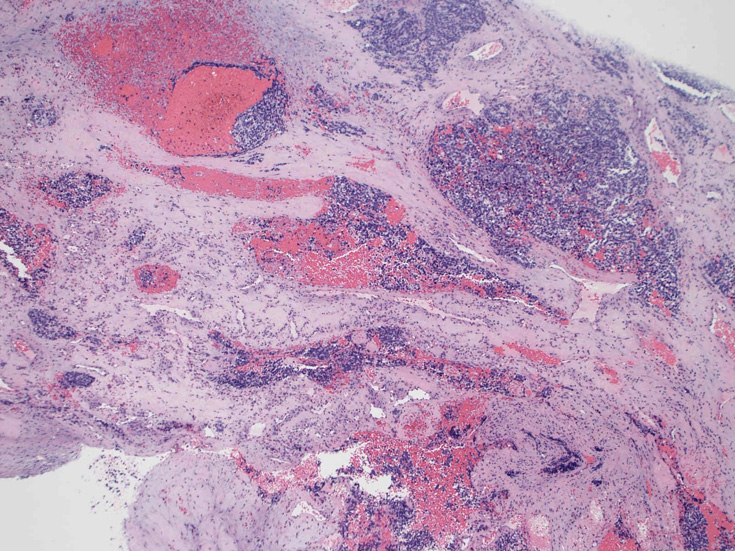

30歳代男性 鼻腔腫瘤の生検組織

厳密にはalveolar patternが明らかではなく, solid typeに入る症例かもしれない。異型細胞増殖胞巣が線維化組織に取り囲まれるように散在している. 小さな生検組織のため全体像が不明である。

loupe01.jpg